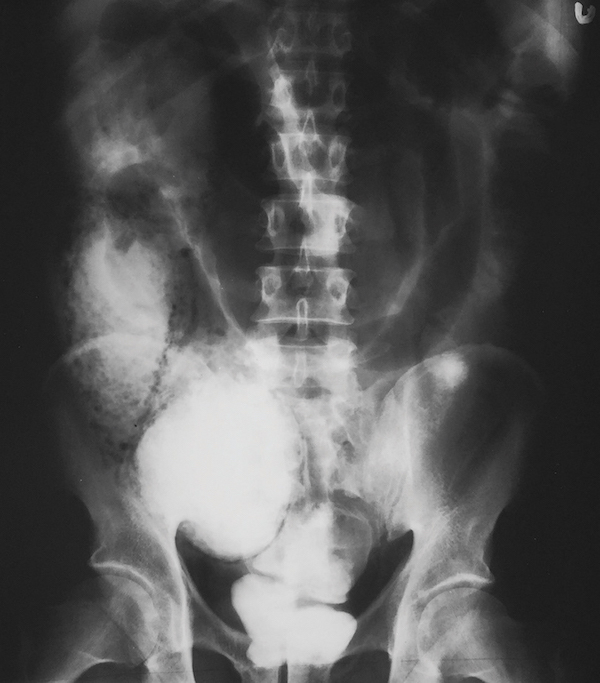

A 58-year-old woman presents to the emergency department (ED) with abdominal pain and distension. She has a history of spina bifida with a neurogenic bladder and chronic constipation, for which she takes an osmotic laxative on a daily basis. She has noted increasing abdominal pain for the week prior to presentation, and she has not passed any stool or gas for 4 days. She reports that she has had progressive abdominal distension and discomfort today, and now has nausea and vomiting, prompting evaluation. On exam, she is morbidly obese, has decreased bowel sounds, and tenderness throughout her abdomen, without guarding or rebound. Rectal examination reveals no palpable stool in the rectal vault. A computed tomography (CT) scan is done in the ED, with the results shown in the figure. Which of the following is the most likely diagnosis?

This woman’s CT scan reveals a sigmoid volvulus, as evident by twisting displacement of the base of the sigmoid colon and mesentery, leading to significant upstream dilation of her colon, with her right colon measuring >15 cm in maximal dimension. Sigmoid volvulus is uncommon, and only accounts for 3-5% of intestinal obstructions, and patients tend to be older with chronic constipation who are institutionalized or have cognitive issues. Management includes urgent endoscopic detorsion, which can help to untwist the colon, and allows removal of air from the proximal distended colon with placement of a decompression tube, with a success rate of 60-80%. Surgery is often performed for patients after the colon has been decompressed in order to prevent recurrence, which is seen in up to 90% of patients. Although a colonic malignancy could cause a mechanical large bowel obstruction, the twisted appearance on the mid pelvis is more suggestive of a volvulus. There is no evidence of free air on the CT scan, so perforation is unlikely. The clinical and radiographic features are not typical for diverticulitis or ileus.